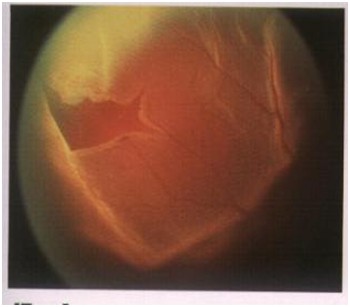

眼底疾病诊治依托北京飞禽走兽 医院著名眼底病专家,不定期进行门诊、手术,拥有一批经验丰富、技术过硬的核心团队。引进先进的蔡司眼底造影系统、德国蔡司最新型号Lumeral T手术显微镜、美国Alcon Accurus 2500转高速玻切机、德国蔡司第四代CIRRUS OCT光学相干断层扫描仪等大型检查及治疗设备,应用现代高科技手段和专家团队技术力量,提供眼底全套检查项目,重点开展玻璃体、视网膜疾病手术及激光治疗,诊疗项目涉及玻璃体切除治疗玻璃体积血、简单或复杂性视网膜脱离、严重眼外伤、糖尿病视网膜病变、晶体异常、黄斑病变、视网膜下新生血管膜、化脓性眼内炎、视网膜肿瘤等多种复杂疑难眼底疾病,其中在糖尿病视网膜病变复杂性视网膜脱离、黄斑病变、眼外伤的诊断及手术等疑难眼底疾病方面有独到的建树。